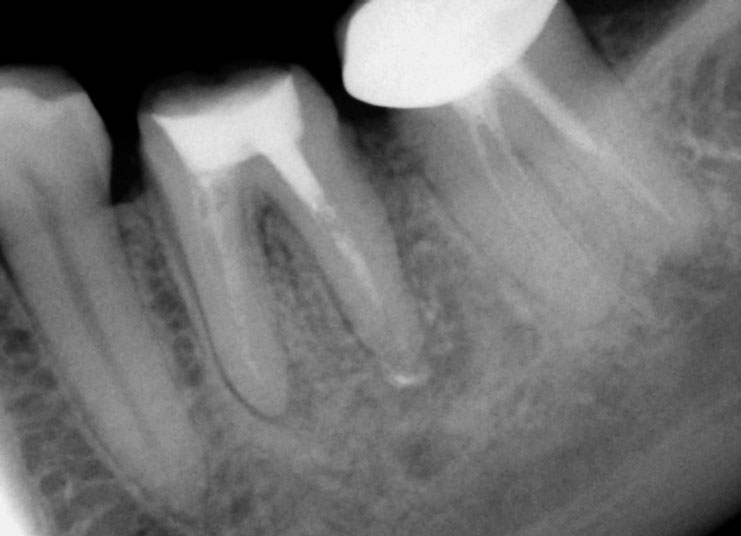

Pre-op

History of persistent swelling in the maxillay first molar despit repeated calcium hydroxide dressings. Patient has undergone multiple “open” and “closed dressings”.

Red arrow shows calcification covering the MB2. Removal of this calcification with ultrasonics reveals the missed MB2(yellow arrow)

5 canals cleaned, shaped and obturated after 10 days of calcium hydroxide. MB1 and MB2 had seperate portals of exit. DB2 merged intoDB1. Palatal two portals of exit.